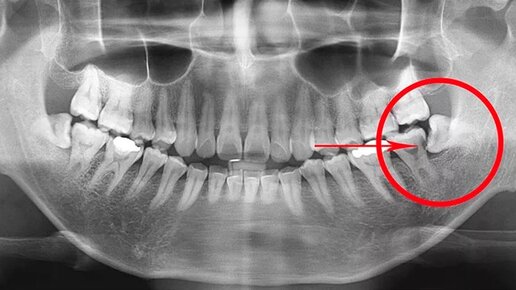

Великолепная восьмерка или ПОЧЕМУ зубы мудрости растут криво